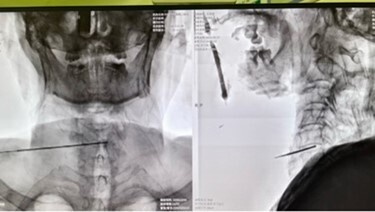

2月底,手术团队为王爹爹进行了手术。借助超声和C臂的引导,他们利用细针从皮肤穿透至受损椎间盘。采用970nm波长的低能量激光,对椎间盘进行了汽化和修复,并加速了软骨化生的进展。这些步骤旨在减轻椎间盘的压力和缓解疼痛。

手术过程顺利进行,患者身上仅存有细微的穿刺点伤痕,出血量非常少。医生凭借精湛的医术,圆满完成了这项技术要求高的手术,为王爹爹的康复带来了新的生机。